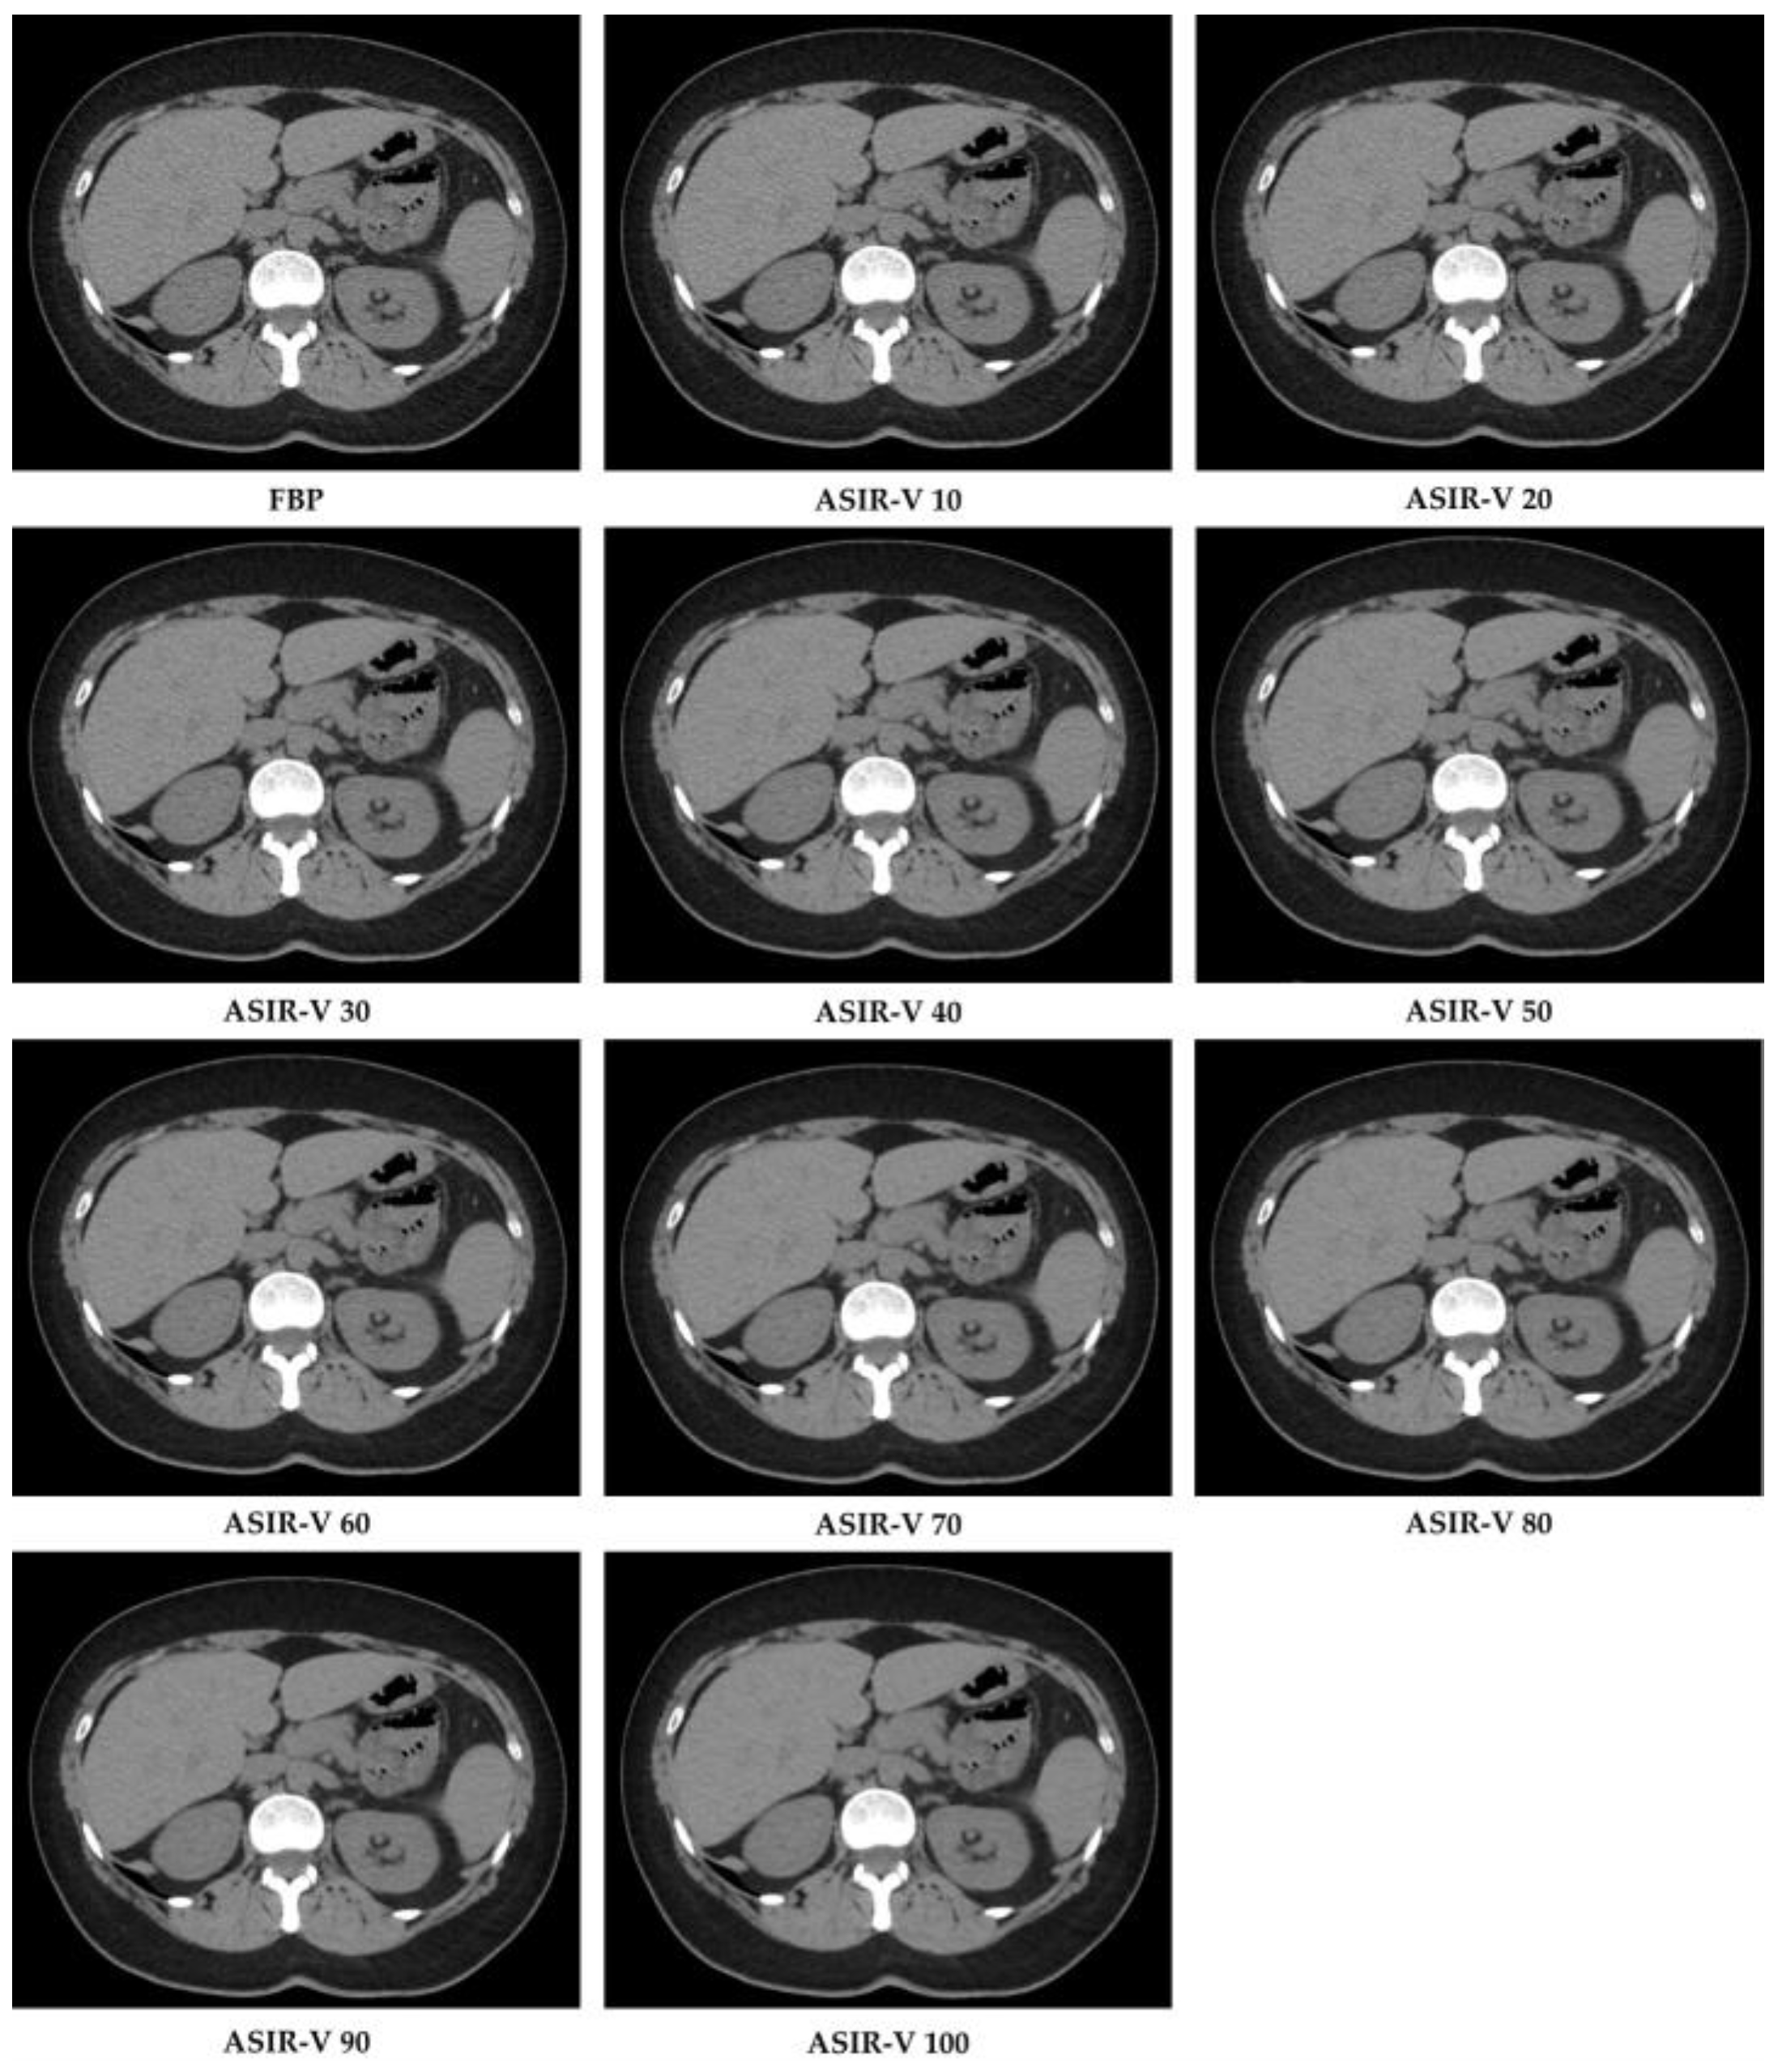

Raw data were reconstructed by choosing two algorithms: FBP and ten different ASIR-V levels (from 10% to 100% with incremental factor of 10), with a slice thickness of 1.25 mm and by using an image matrix of 512 × 512 pixels with the standard kernel. In total, this resulted in 11 image datasets per patient (Figure 2).

Figure 2.

CT image reconstructions at filtered back projection (FPB) and at different Adaptive Statistical Iterative Reconstruction-V (ASIR-V) levels.